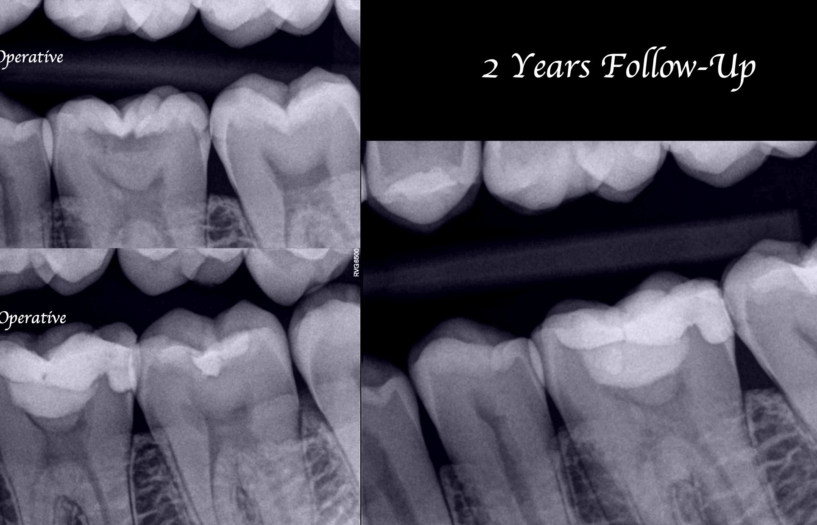

One of the main characteristics of Biodentine is that it is easy to manipulate, it can be used as a dentine substitute due to its high compression strength and offers good adhesion to the tooth structure. Its characteristics mean that it is easy to place it in the region to be treated and can be used as a base for the definitive adhesive coronal restoration. Fig. 9 shows the vital pulp therapy procedure. In radiographic form, on follow-up after two years, it is possible to observe mesial pulp horn retraction. One of the most appreciated advantages of Biodentine is that it does not pigment the tooth structure, making it an ideal material for performing pulp capping in the anterior sector.

Fig. 9. Vital pulp therapy at tooth no. 19 . At follow-up after 2 years the retraction of the mesial pulp horn can be seen